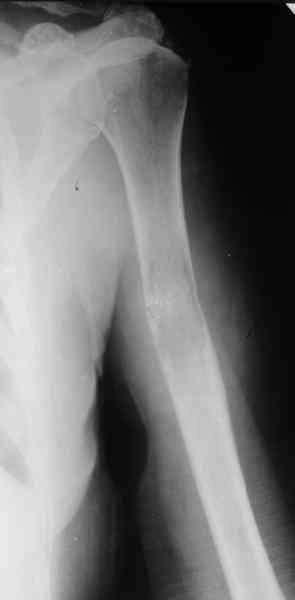

Женщина 53 лет получила патологический перелом правого плеча в

феварле, и левого в марте - mts из невыясненного первичного очага.

На нас вышли родственники. Состояние пациентки уже не очень, анемия

(Hb -50-60 г/л), исхудалв, но асцита нет, в легких чисто. Поскольку

женщина совершенно беспомощна, решили сделать остеосиннтез.